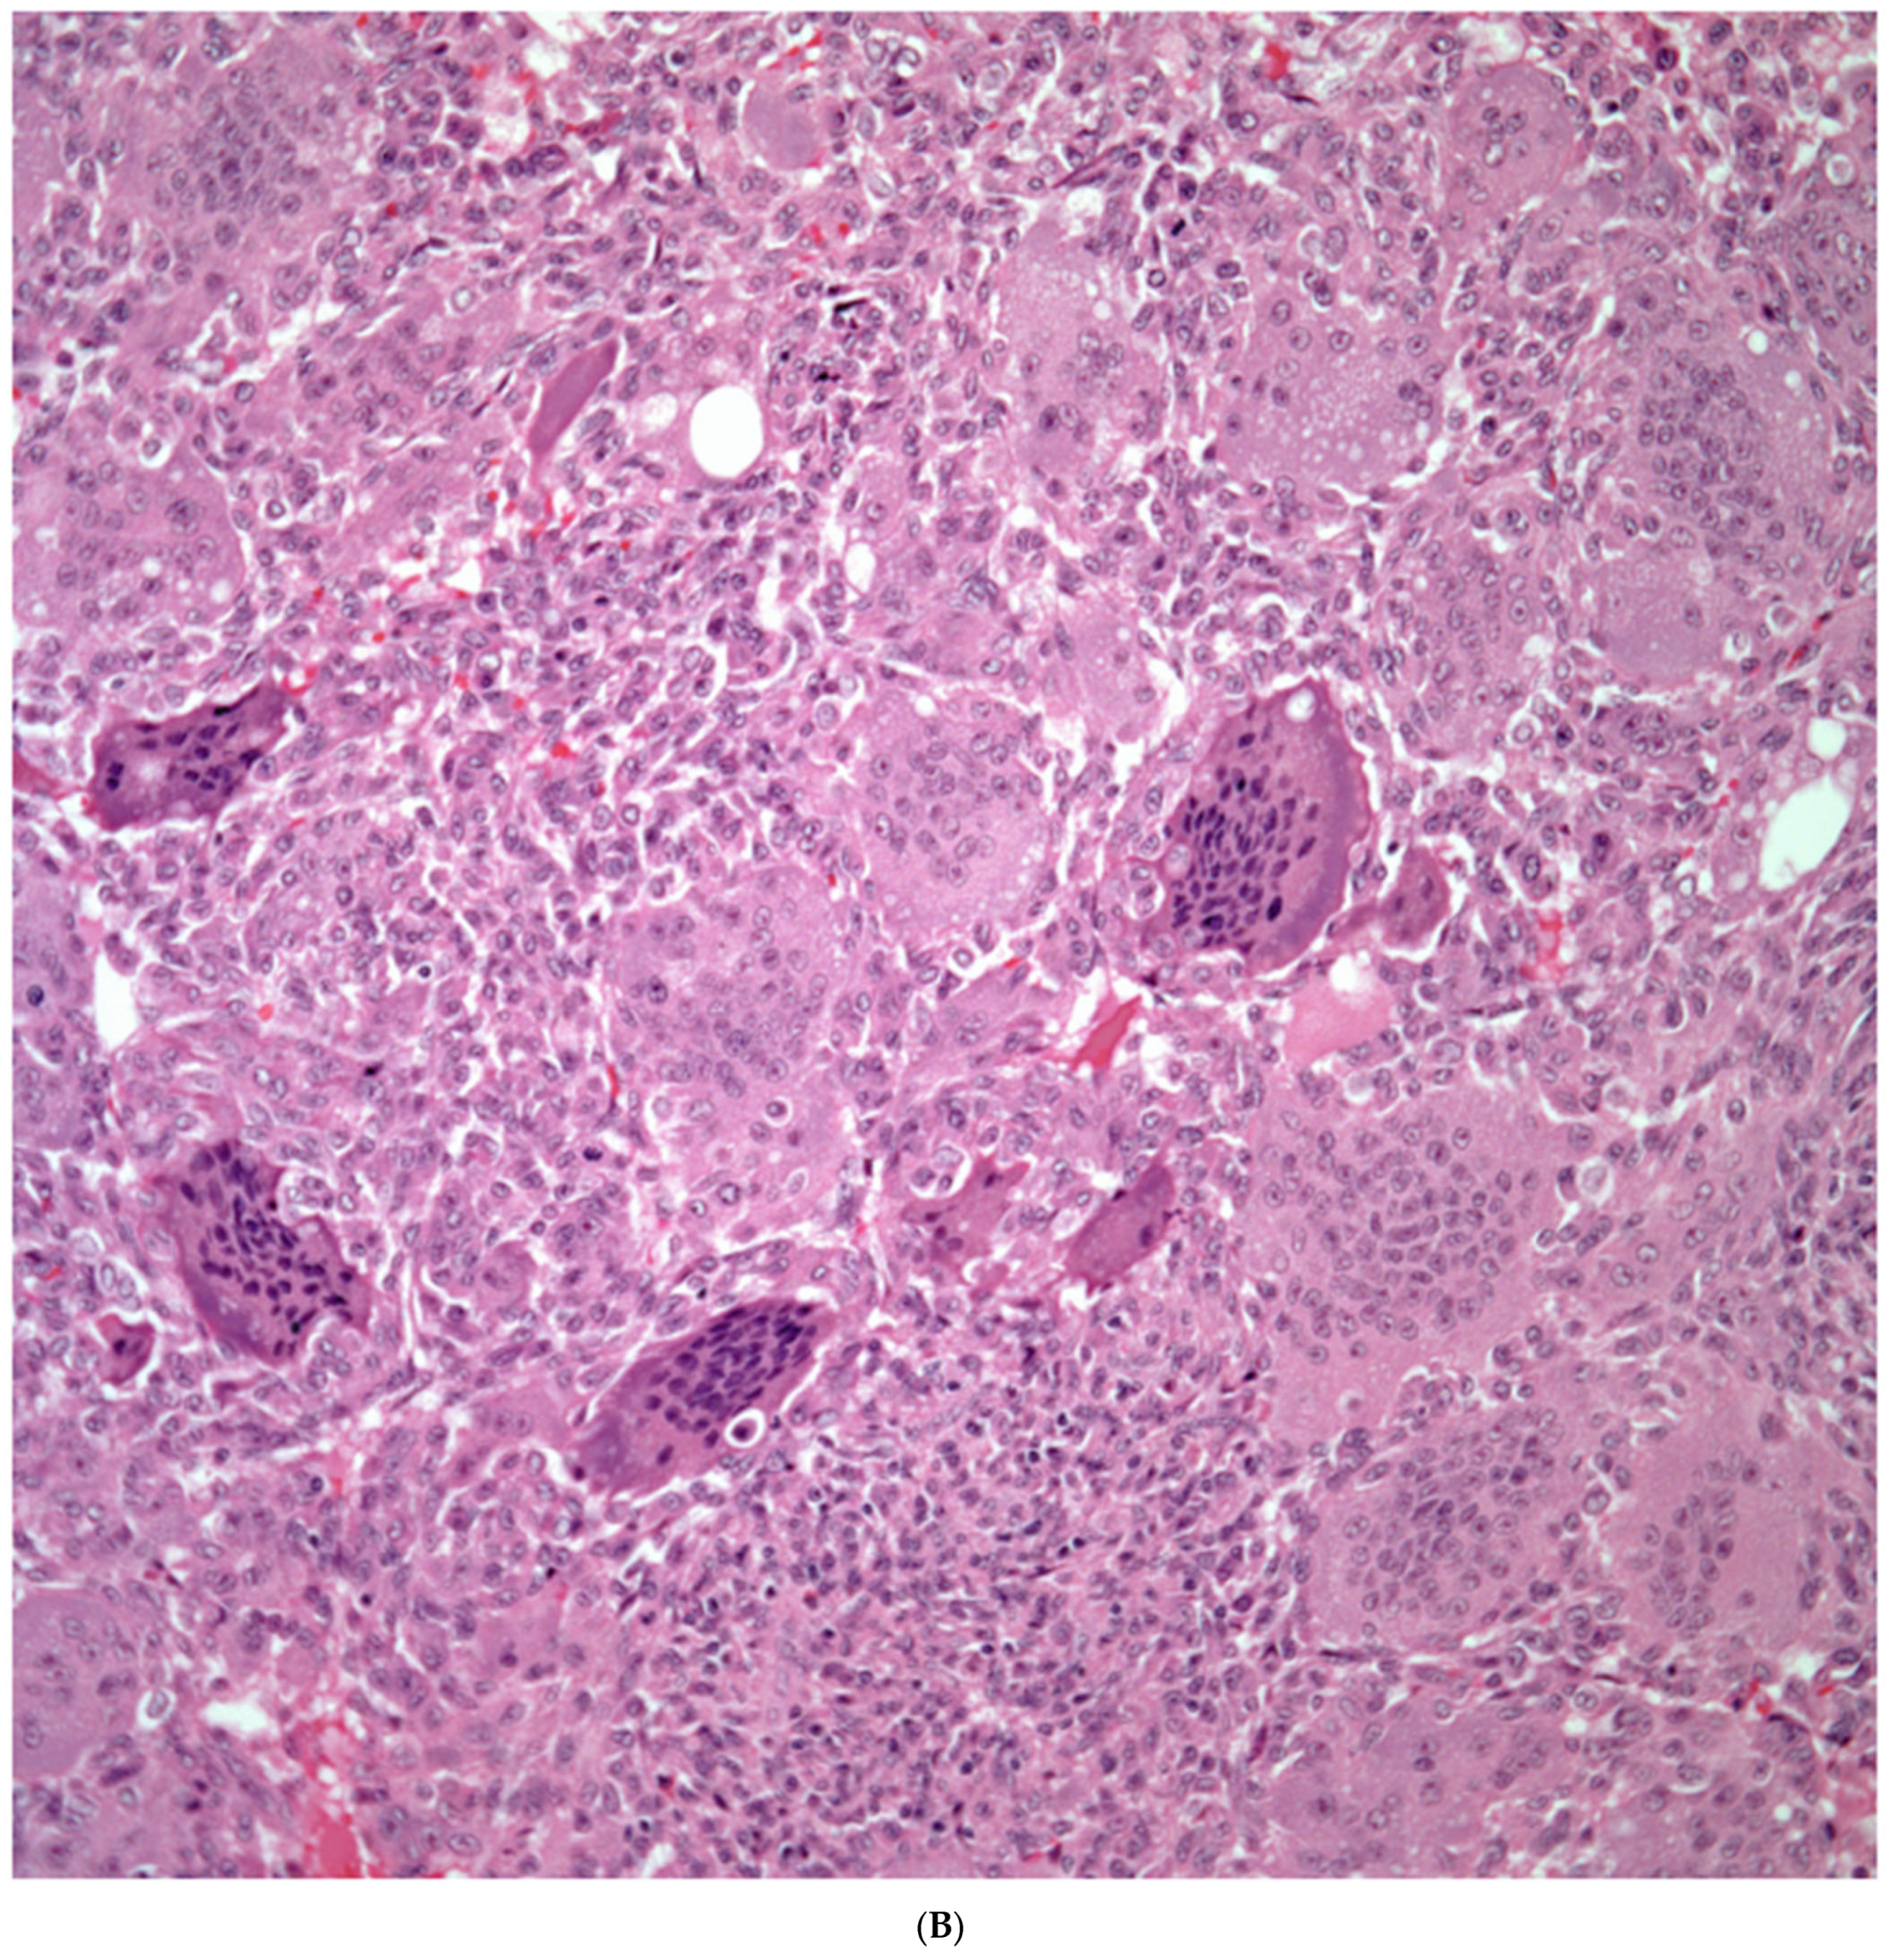

Giant Cell Carcinomas: These tumors may show predominantly a neoplastic cellular proliferation composed exclusively of multinucleated giant cells or a predominantly giant cell carcinoma (Figure 5A,B) or associated with a conventional non-small cell carcinoma like adenocarcinoma or squamous cell carcinoma. The giant cell carcinoma may show giant cells of the syncytiotrophoblastic, osteoclastic, or null cell type. The giant cell carcinomas of the null cell type characteristically show a prominent inflammatory background and giant cells engulfing inflammatory cells (emperipolesis) (Figure 6A,B). The tumors composed of osteoclast-like giant cells show giant cells like those described in bone tumors (Figure 7A,B).

Figure 6.

(A) Giant cell carcinoma, null cell type, note the inflammatory background; (B) Malignant giant cells with inflammatory cells and focal emperipolesis.